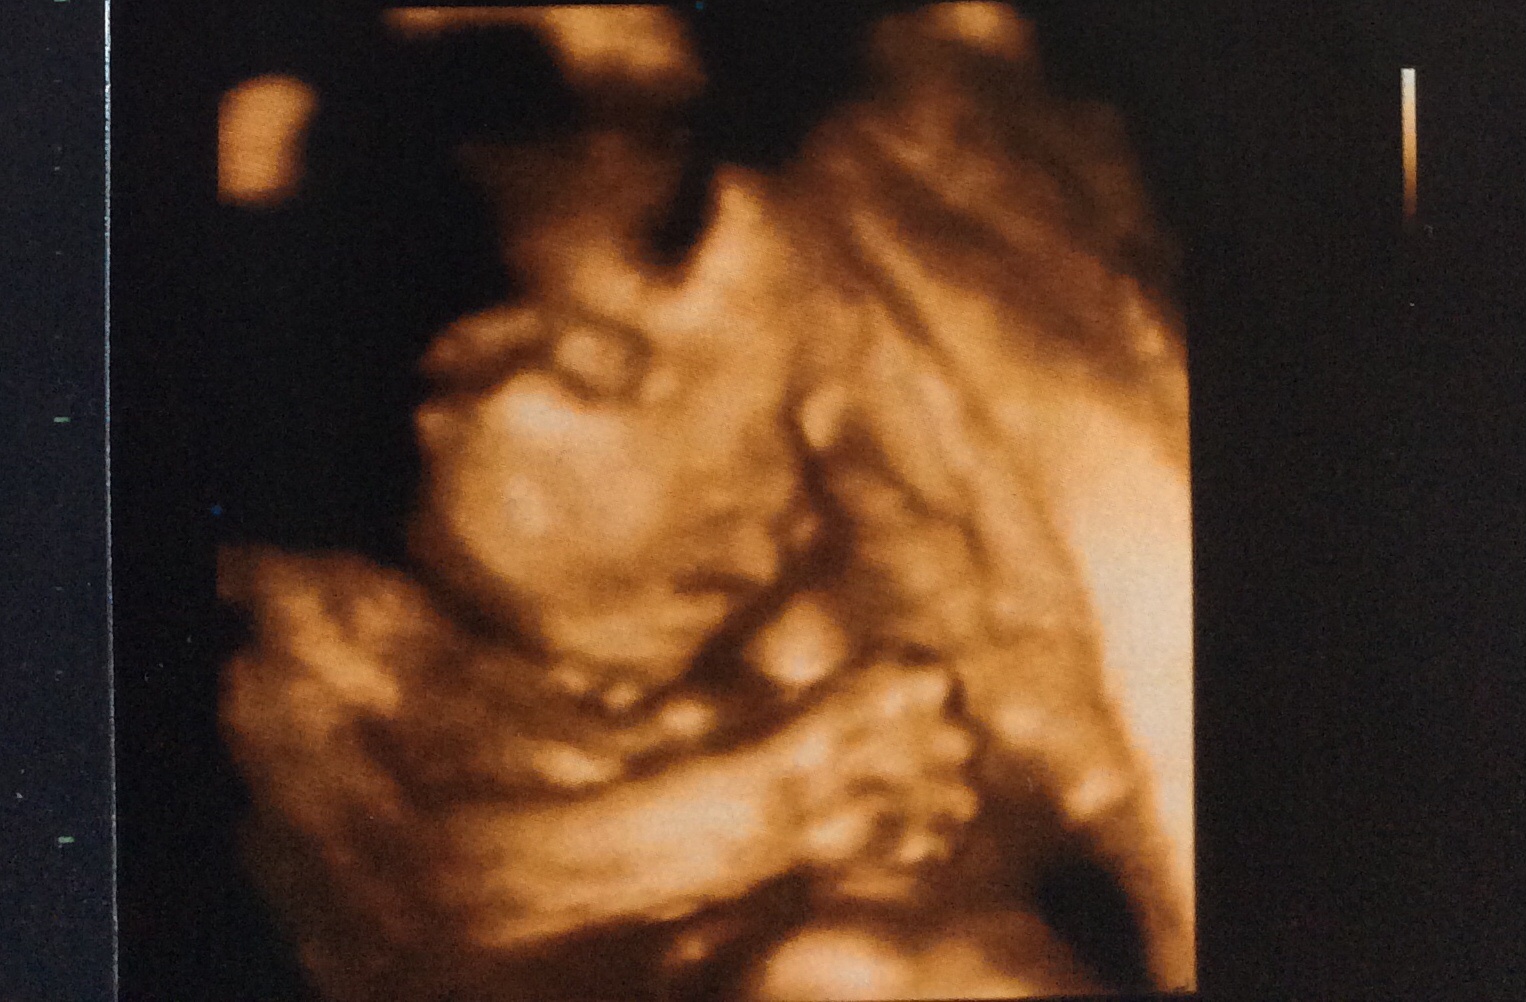

ภาพ ซาวน์์น้อง แบบนี้ มีดั้งไหมค่ะ

ตื่นเต้น จังค่ะ